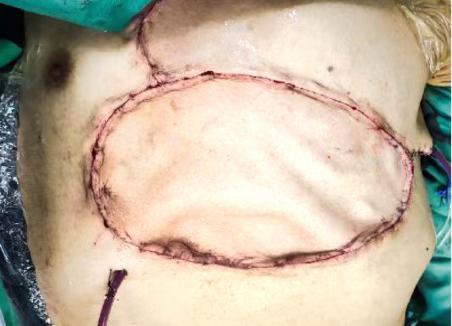

皮瓣是从其原所在位置部分或全部切取,用于修复身体其他部位皮肤缺损的一块皮肤和皮下组织。皮瓣在形成过程中必须有一部分与本体相连,此相连的部分称为蒂部。皮瓣的血液供应与营养在早期完全依赖蒂部,皮瓣转移到受区,与创面受区重新建立血液循环后,才完成皮瓣转移的全过程。

如果把皮肤视为绿茵场,皮瓣就像是一块草皮,皮瓣移植就是将一处草皮,根据需要移植到另一处,并且确保移植后的皮瓣正常生长,发挥作用,而且皮瓣这块“草皮”,自带灌溉系统和肥沃土地,可以实现“自给自足”。

图1 版权图片 不授权转载